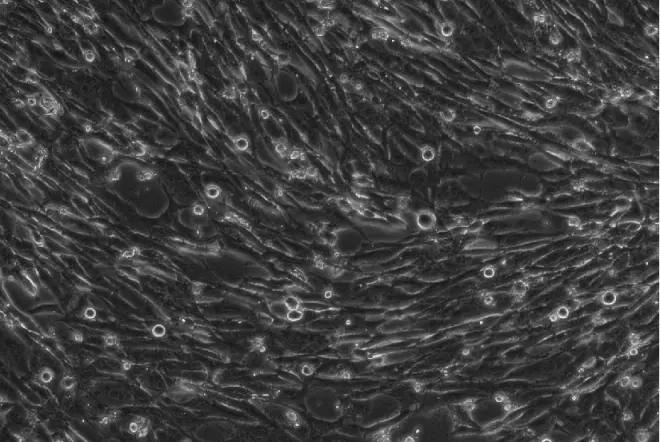

正常HFF细胞呈密集分布的长梭形,三角形

在HFF细胞培养液中加入500ul的病毒上清,放入37℃ 5%Co2培养箱中继续培养,观察HFF细胞随着AD169病毒感染时间延长而发生的形态变化: 感染第1-6天:HFF细胞胞体发生轻度肿胀,细胞排列紊乱 第一天